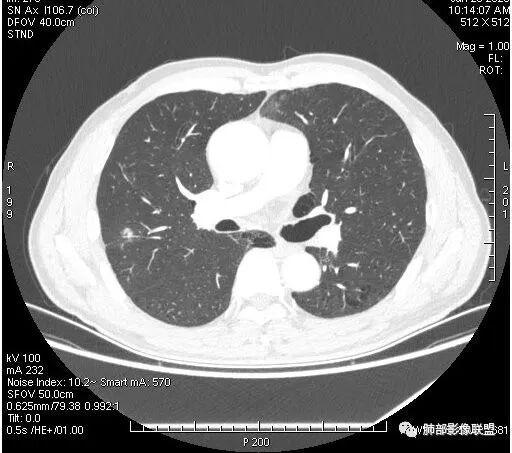

右肺上叶后段占位病灶,病灶不规则,周围胸膜线性牵拉,病灶部分周围有晕,病灶内见不规则空洞,未见明显引流支气管,长毛刺,多分叶、肿块边缘部分L型,可见血管直接供养。增强见点状坏死、病灶内血管。综上考虑恶性可能性大,鉴别隐球菌。

右肺上叶结节,浅分叶膨隆,边缘可见胸膜牵拉及血管集束,不规则厚壁空洞,不均匀强化,血管进入病灶,边缘毛燥,考虑低分化腺癌,鉴别隐球菌。

右肺团块影,深分叶,有毛刺,但毛刺偏软。团块附近有血管走行,穿过。血管增粗,僵直。空洞近心,团块周围似有卫星灶。良,恶性征象都有;按可能性排序:隐球,结核,腺癌。

晨读,右肺上叶结节,边缘膨隆、分叶,部分边缘有平直,可见多发毛刺及胸膜牵拉,牵拉线清秀,收缩力弱,内密度不均,可见片状低密度影及空洞,增强后不均匀强化,血管集束,考虑良性,肉芽肿性结节,鉴别腺癌

晨读:双肺胸膜下多发小气囊,大小不一,右肺结节,内部可见小空洞,洞壁光滑,厚薄不一,偏心性生长,近段血管束增粗,有分叶,毛刺(软),有晕征,平扫密度尚可,增强后不均匀强化,可见低密度坏死,及部分血管穿行,体检发现,考虑恶性:腺癌,鉴别炎性结节

晨读:男,67岁,体检发现右肺结节。近圆形,支气管及伴行血管进入结节,进入结节后支气管堵塞,血管走形尚自然,结节内血管边缘凹凸不平。远端边缘见毛刺(软毛刺?)及分叶。见胸膜牵拉。实变中见空洞。整体膨胀感不明显。考虑炎性肉芽肿可能,隐球菌病可能性大。注意鉴别鳞癌、结核。

这个病例确实有很多隐球菌的特点,包括周围的卫星灶、周围的毛刺,它没有粗短的毛刺,它是稍长一点、柔弱一点的。我是觉得这个符合脐凹征,所以我觉得恶性不能排除,结果错了,是炎性。

这个大部分边缘稍微偏平直一点,血管走行非常自然,包括里面的空泡征样的,影子很干净,边界很光滑,都是些炎性特点。